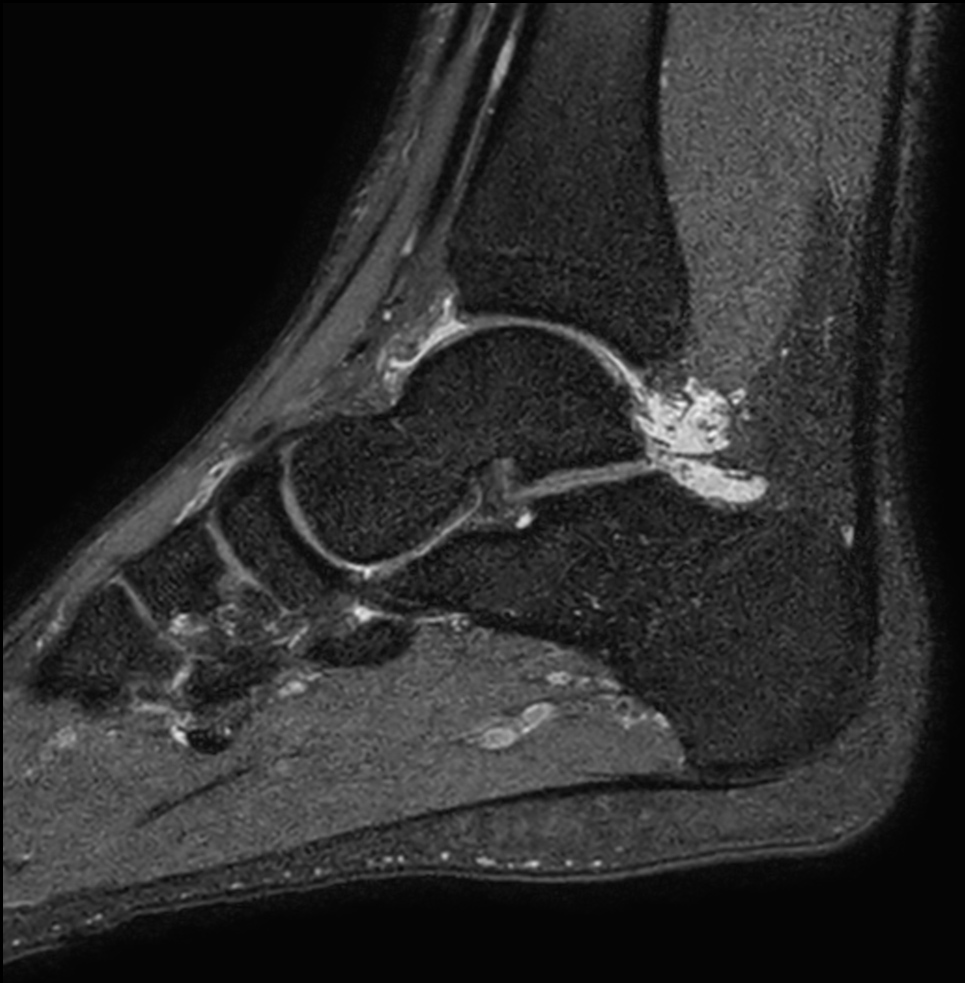

High resolution Ankle imaging in short scan times

Spital Uster, Switzerland

Sagittal 3D PDw SPAIR (0.6 mm, 7 min)

Sagittal 3D PDw SPAIR (0.5 mm, 7 min)

Sagittal 3D PDw SPAIR (0.5 mm, 5 min)